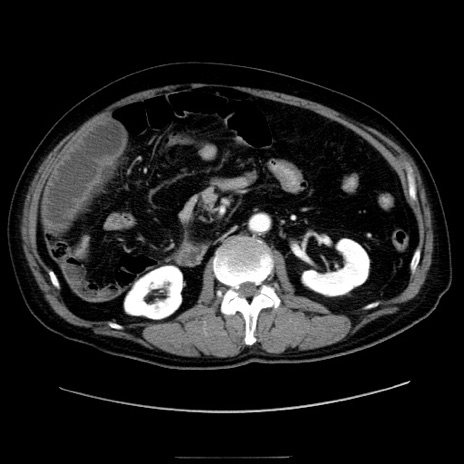

冠状断像

【症例】80歳代男性

【主訴】臍周囲痛

【現病歴】約6時間前から臍下部痛が出現。次第に腹部膨隆・背部痛も生じてきたため来院。背部痛の場所は変化しない。

【既往歴】腎盂腎炎

【身体所見】意識清明、BT 36.3℃、BP  131/87mmHg、P 87bpm、SpO2 100%(RA)、臍周囲自発痛・圧痛あり、反跳痛なし、自発痛部位に一致して板状硬あり、腹部膨隆、腸雑音減弱、CVA tenderness両側陰性。

【データ】WBC 19600、CRP 0.33